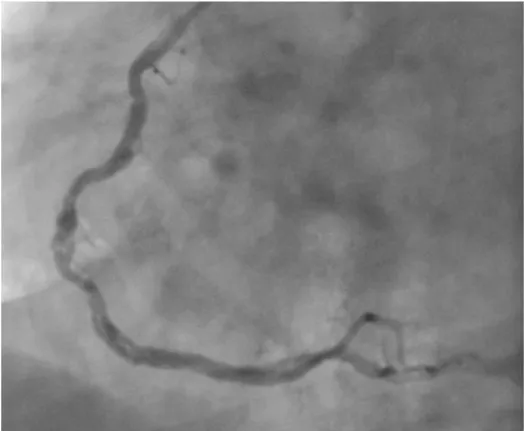

Recently, we have encountered a case of WCA associated with myocardial infarction. A 46-year-old man presented cardiology department with stable angina pectoris. An electrocardiography (ECG) showed Q waves in the inferior leads. Echocardiography examination showed akinesis of the inferior wall and left ventricle ejection fraction was 50%. The coronary angiograms showed a 70% stenosis of left anterior descending artery (LAD), 99% stenosis of circumflex artery and a twisting course of the right coronary artery lumen after it divided into multiple channels (woven right coronery artery) (Figure 1, Video1). He was transferred to the cardiovascular department for the bypass surgery.

Figure 1: Coronary angiography revealed woven coronary artery anomaly at the mid segment of the right coronary artery.